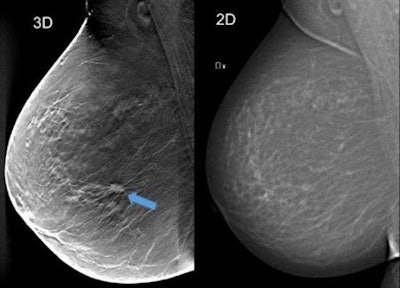

Using breast tomosynthesis (3D screening) in the image to the left (one of about 50 thin cross-sectional image slices of the breast), you can see an approximately 1 cm-large tumour that is not clearly visible on the mammography image on the right, even though the breast does not contain particularly dense tissue. Image courtesy of Skåne University Hospital in Malmö."If supported by cost-effectiveness studies, one-view digital breast tomosynthesis warrants consideration as the preferred breast cancer screening method in the future," she and her colleagues wrote (Lancet Oncology, October 12, 2018).